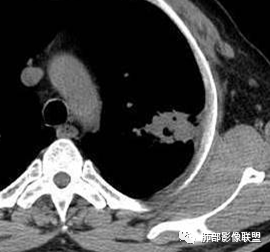

糊墙:肺内病灶不侵犯壁层胸膜或以外,与壁层胸膜相对而言分界清楚。

栽赃:病灶侵入壁层胸膜及胸膜外脂肪间隙、胸壁其他结构等,相对在病灶中央区域,与胸膜分界不清。

这是糊墙。

这就栽赃。都突到外面去了。

看看这个,骨头都侵袭了。

南边:一般这类侵袭,是中央地带毛刷状延伸到胸膜内。

南边:栽赃是这样过去的,中间不会脂肪间隙清晰。